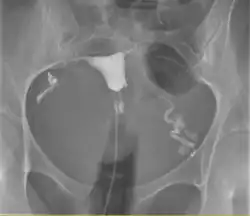

L'hystérosalpingographie est un examen de radiologie qui permet de visualiser l'utérus ainsi que son col et les trompes de Fallope.

On commence par introduire dans le vagin un spéculum. Ensuite on place sur le col de l'utérus une sonde ou des pinces selon la morphologie du col, afin d'assurer l'étanchéité entre l'utérus et le matériel d'injection. Ensuite on gonfle le ballonnet et on injecte dans l'utérus, puis dans les trompes, un produit de contraste, souvent à base d'iode, qui est opaque aux rayons X. On prend ensuite plusieurs clichés radiologiques au fur et à mesure de la diffusion du produit. On suit le parcours dans l'appareil génital du produit, lorsqu'il remplit puis désemplit l'utérus. Remarque : Cet examen ne permet pas l'exploration des ovaires. Cet examen nécessite un test Beta HCG négatif le jour de l'examen, réalisé dans les 48h avant ("test de grossesse par analyses de sang"), la prise d'antispasmodiques la veille au soir et les heures qui suivent l'examen, et éventuellement d'antibiotiques oraux et vaginaux la veille et les jours qui suivent l'examen.

Il y a d'abord un premier cliché sans l'ajout du produit de contraste qui permettra par la suite de visualiser l'appareil génital. On introduit ensuite le produit de contraste avec du matériel à usage unique. À l'aide d'une petite sonde positionnée dans le col utérin, un liquide à base d'iode est introduit dans l'utérus puis les trompes, il s'agit du produit de contraste, pour qu'il ne sorte pas immédiatement pas le col, on gonfle un ballonnet de manière que le produit remonte vers les trompes.

Des clichés sont pris en cours de remplissage de l'utérus et des trompes suivis d’un cliché tardif (20 minutes après la fin de l’examen).